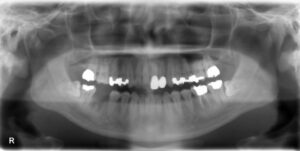

上顎臼歯3本欠損症例

BEFORE AFTER 75歳女性/上3本欠損/インプラント埋込手術 【治療内容】 左上に第一小臼歯と第二大臼歯を繋ぐ…